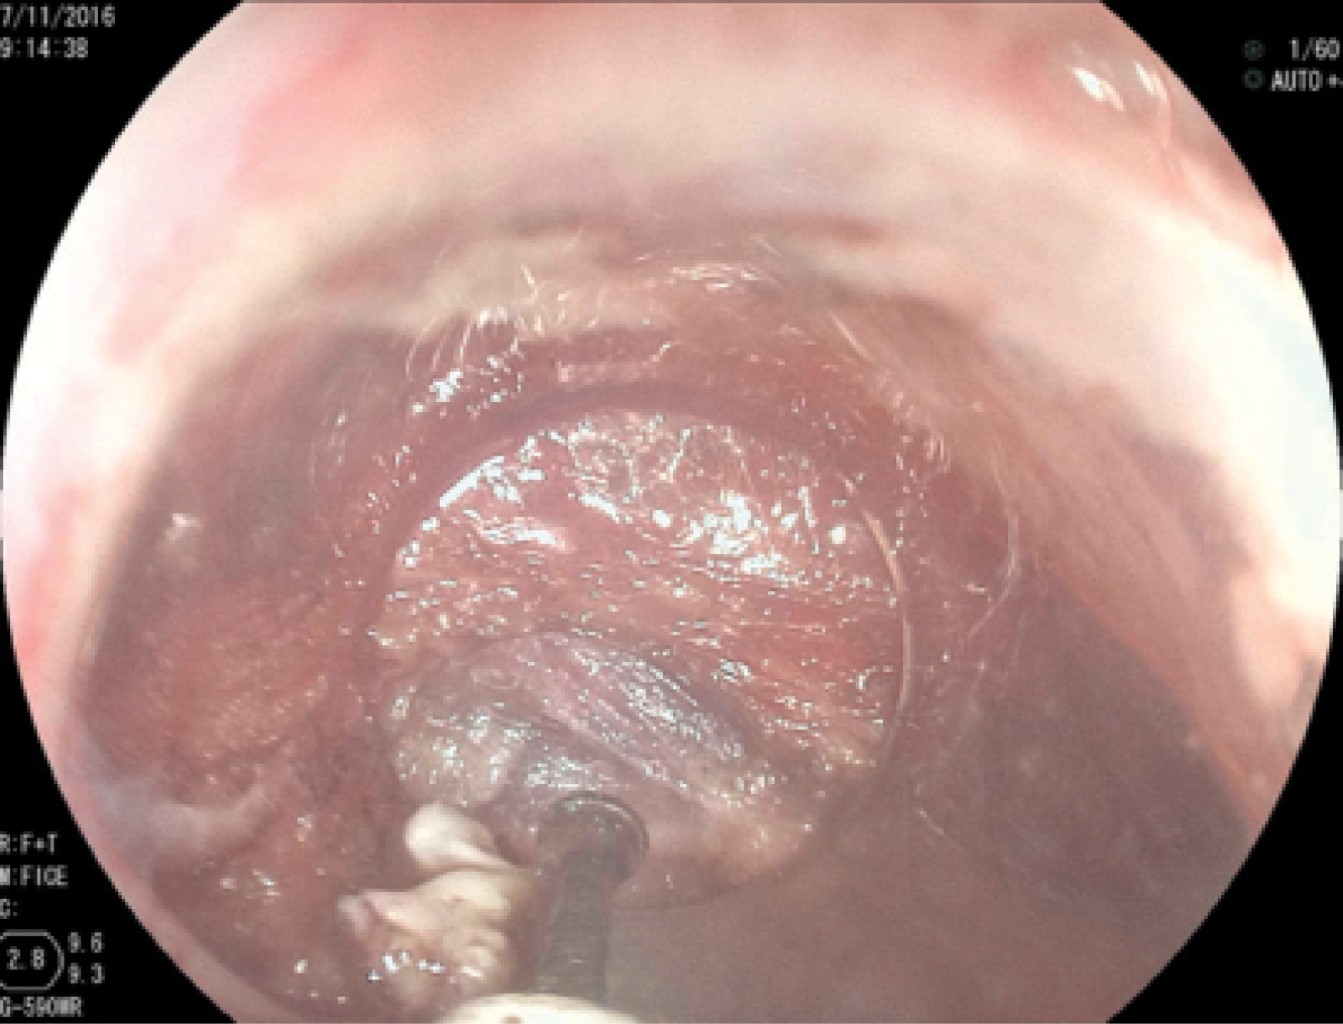

En los primeros 10 pacientes una vez identificada la luz del esófago, se introdujo una guía metálica a la cavidad gástrica y sobre ésta un dilatador de Savary Gilliard de 7 mm o 21 Fr, el cual llega hasta el estómago y se deja en ese sitio. Lo anterior delimita adecuadamente la luz del divertículo y del esófago (Figura 2). En el extremo distal del tubo de inserción del endoscopio se coloca un capuchón plástico transparente (MBL 6-1 Cook Endoscopy) que se utiliza como espaciador, lo que permite identificar el septum del músculo cricofaríngeo. En los primeros 10 casos se utilizó un videogastroscopio Olympus modelo GIF-H140 y procesador de imagen CV-140 Olympus (Olympus Optical Co., Tokio, Japón) de 9.8 mm de diámetro, la unidad electroquirúrgica Olympus UES-40 SurgMaster, y como disector un cuchillo aguja (Needle Knife, Cook Endoscopy, Winston-Salem, NC), se hace un corte en el borde de la luz esofágica en la parte media del septum y hacia la luz del divertículo. Se realiza primero el corte de la mucosa exponiendo las fibras musculares del cricofaríngeo (Figura 3), el corte se profundiza hasta completar la sección de las fibras transversales del esfínter cricofaríngeo, sin necesariamente llegar al fondo del divertículo (Figura 4), lo que permite la aproximación de los bordes de la incisión en la mucosa con clips metálicos evitando la perforación y riesgo de sangrado (Figura 5). A los cuatro pacientes restantes se les aplicó la técnica de POEM (miotomía endoscópica peroral), infiltrando la submucosa con solución fisiológica y azul de metileno para levantar la mucosa, posteriormente, se corta la mucosa con el hidrodisector HybridKnife, tipo T-type marca ERBE que es un instrumento multifuncional que combina tecnología electroquirúrgica e hidrodisección en un solo instrumento con el cual se realiza un levantamiento de la mucosa y la creación de un túnel submucoso, seccionando sólo las fibras musculares transversales y finalmente cerrando la entrada del túnel con clips endoscópicos. En estos pacientes se utilizó un videogastroscopio Fujinon, procesador de imágenes Fujifilm Processor VP-4450HD, unidad electroquirúrgica ERBE VIO 200 D y el HybridKnife de ERBE, T-type (marcas registradas) utilizando corriente de corte y coagulación pura (50 W). Por último se retira el dilatador de Savary Gilliard y posterior al procedimiento se efectuó un trago de material hidrosoluble para descartar fugas. A todos los pacientes se les administró una dosis única de antibiótico al inicio del procedimiento y fueron manejados de forma ambulatoria en domicilio iniciando con dieta líquida a las cuatro horas.

Figura 4